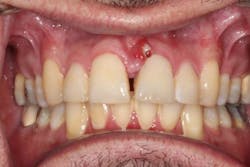

A 49-year-old male presented with pain at tooth no. 9. A labial fistula was clinically present (figure 1).

A review of the patient’s dental history revealed a very recent visit to a dentist for a laser surgical procedure. More than likely, improper use of the dental laser caused overheating of the bone and trauma to this area, ultimately resulting in bone necrosis and sequestra. Both hard- and soft-tissue loss resulted, and an abscess denoting infection occurred.

Because this is a maxillary anterior area in the esthetic zone, it will require interdisciplinary management and a high financial cost to the patient to correct the problem. Tooth rotation, the presence of a diastema, interproximal papilla, gingival margins and contours, as well as tooth size will all be addressed.